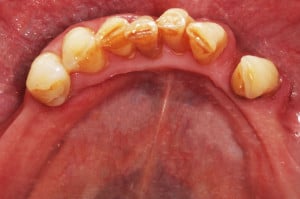

Pacjentka lat 65, zgłosiła się do stomatologa na konsultację, ponieważ niepokoiła ją ruchomości zębów. W pierwszej kolejności została skierowana na wizyt higienizacyjną. Bezzębie w łuku górnym zaopatrzone było całkowitą akrylową protezą, w łuku dolnym pacjentka nie użytkowała żadnego uzupełnienia. Pacjentka niepaląca.

Postępowanie rozdzielono na dwie wizyty. Badaniem klinicznym, oceniając wskaźniki periodontologiczne, uzyskano wartości API 100%, PBI 100% świadczące o konieczności poprawy higieny i procesie zapalnym dziąseł, duże złogi kamienia nad i poddziąsłowego, bardzo obfity biofilm, pogłębione wszystkie kieszonki dziąsłowe, ciężkie zapalenie dziąseł, ruchomości zębów dolnych III stopnia, duży zanik kości. Badanie kliniczne błony śluzowej jamy ustnej nie wykazało zmian patologicznych.